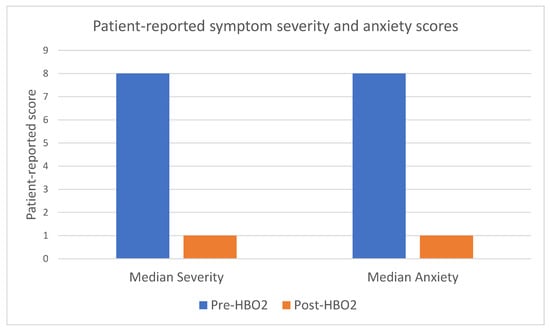

Background/Objectives: To determine long-term patient-reported outcomes for patients undergoing hyperbaric oxygen therapy (HBO2) following external beam radiotherapy. Methods: A retrospective cohort study of all consecutive patients who underwent HBO2 for radiation cystitis in South Australia from September 2017 to March 2023 was performed. Patient-reported symptom severity, anxiety, healthcare use and transfusion requirements pre- and post-treatment were collected through telephone interview. Readmission data and procedural data was collected through both telephone interview and a state-wide electronic medical record. Jamovi was used to perform paired sample t-tests for statistical analysis. Results: There were 89 patients who underwent HBO2 for radiation cystitis with 54 completing the questionnaire. There were 85% of patients alive at the time of follow-up, with 61% of the total cohort and 74% of survivors completing the questionnaire. For those completing the questionnaire, 96% were male with all of them having prostate cancer. Median age was 74 (interquartile range [IQR] 69–78). The mean reduction in patients’ perceived symptom severity after HBO2 on a scale out of 10 was 7.9 to 2 with a difference of 5.9 (95% confidence interval [CI] 5.1–6.7, p < 0.001) and the mean reduction in perceived anxiety was 6.9 to 2.1 with a difference of 4.7 (95% CI 3.6–5.8 p < 0.001). Patients reported a reduction in family doctor visits from 2.7 to 0.76 with a mean reduction of 2 (95% CI 0.8 to 3.2, p = 0.003), emergency department presentations from 3.3 to 0.57 with a mean reduction of 2.7 (95% CI 1.4–4.1, p ≤ 0.001) and blood transfusions from 0.67 to 0.31 with a mean reduction of 0.34 (95% CI −0.44 to 1.1, p = 0.017). Ongoing haematuria was reported in 21 of the 54 patients (39%). Further treatment was required for 20 patients (25%). No patients reported any severe or ongoing adverse effects from HBO2 via the questionnaire. Conclusions: HBO2 is a safe option for recurrent haematuria due to radiation cystitis with high patient satisfaction and reduction in patient-perceived symptom severity, anxiety and healthcare utilisation. Level of evidence: 4.